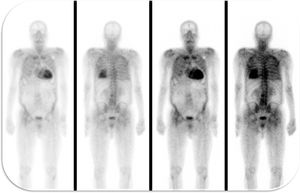

The following year, he developed NYHA class II to III congestive heart failure (HF), requiring uptitration of diuretics. The repeat echocardiogram showed moderate concentric left ventricular hypertrophy, with preserved ejection fraction but an abnormal global longitudinal strain and elevated filling pressures (Figure 3). He repeated the coronary angiography which excluded CAD progression. He underwent a 99mTc-DPD scintigraphy that revealed significant myocardial tracer uptake, diagnosing TTR amyloid infiltration (Figure 4). He was stabilized with medical therapy and kept under close follow-up, requiring antianginal therapy uptitration for exertional microvascular angina.

In our clinical case, the patient presented with microvascular angina, a rare symptom of cardiac infiltration. The only findings from his medical history that were in keeping with the suspicion of an infiltrative disease were the bilateral carpal tunnel syndrome and the atrioventricular block.8 The echocardiographic findings suggestive of myocardial infiltration were present only when the patient developed HF, after 4 years of medical follow-up. At that time, the 99mTc-DPD scintigraphy was consistent with TTR infiltration. This technique has been shown to be specific for cardiac involvement in TTR amyloidosis, with mild or no tracer uptake in patients without cardiac involvement9 or in patients with other types of systemic amyloidosis.10 As a consequence, 99mTc-DPD scintigraphy is recommended as a diagnostic test for TTR cardiac amyloidosis in the European guidelines.11